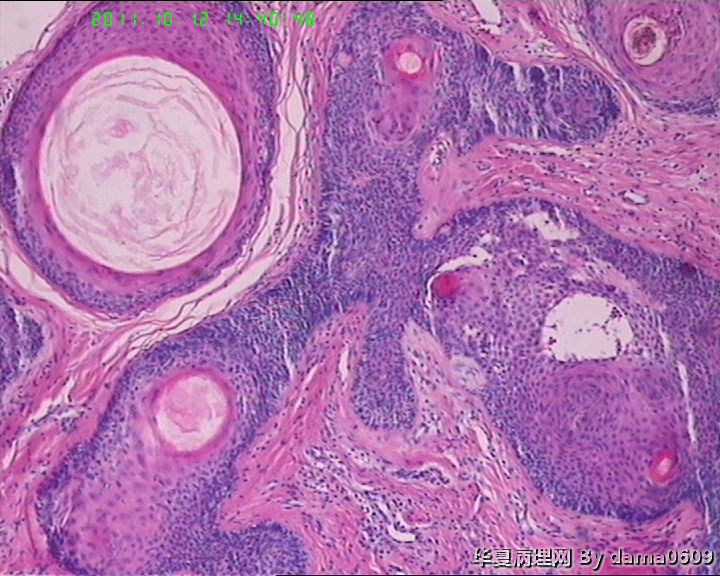

女,42岁,右眼外上方皮下肿物4年。

送检:椭圆形肿物,v:0.5x0.5x0.4cm,实性,灰白色,质软。

• 眼角旁皮下肿物,不会了啊!!图2

图2

毛发腺瘤

看起来,是否要考虑毛发上皮瘤?

镜下大部分都是毛囊结构,要考虑毛囊痣。